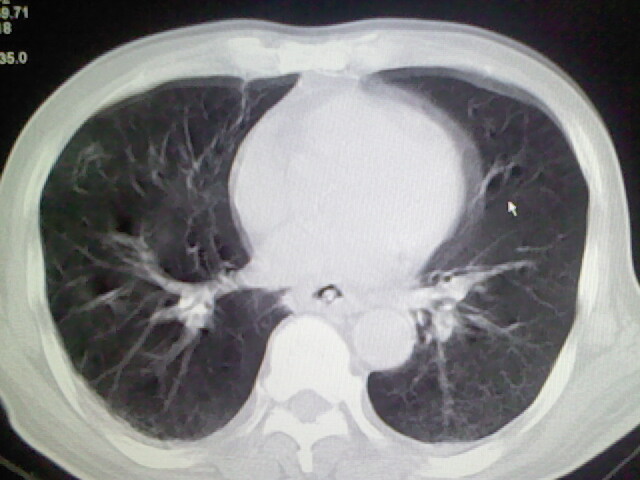

男,70岁,脑出血,长期卧床,左侧背部可触及肿块

右肺病灶考虑炎症性。

考虑右肺及左肺下叶炎症。

考虑右肺及左肺下叶慢性炎症。

右侧肺部见片状密度增高影,边缘模糊。考虑炎症。另食管壁增厚。

右肺上叶前段病呈楔形,其尖端指向肺门,考虑肺动脉栓塞可能性大.